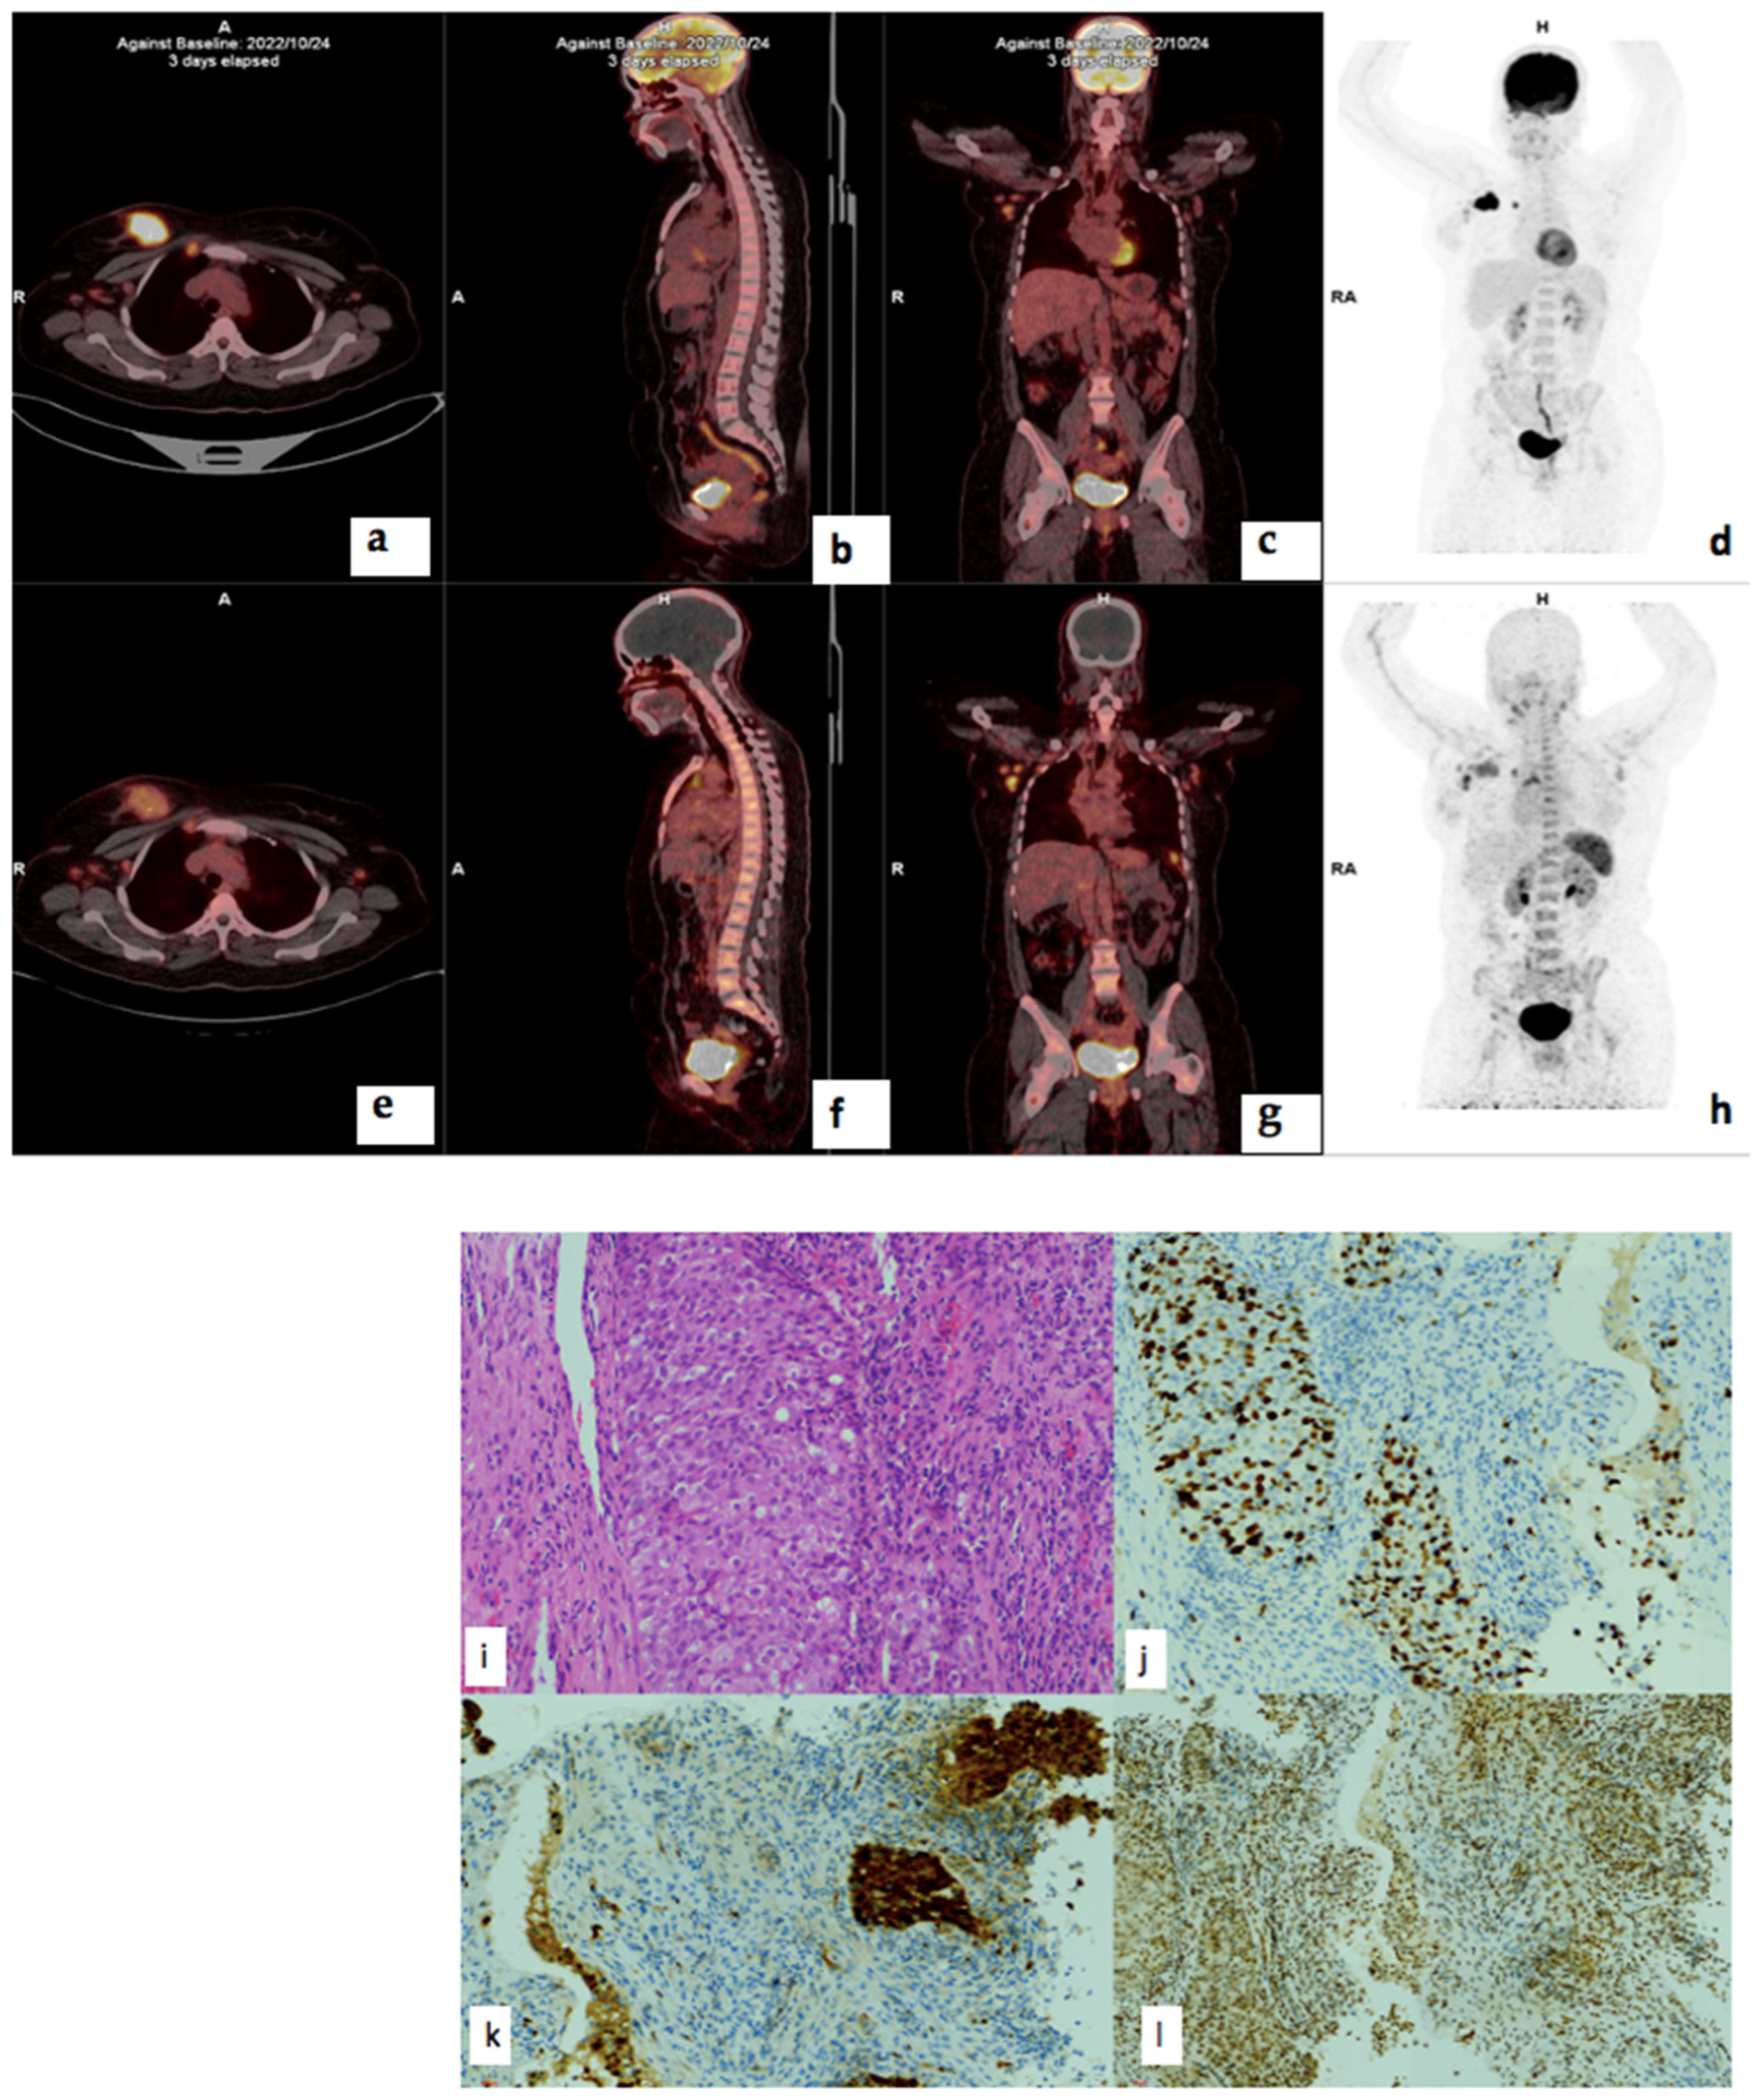

Figure 8.

18F-FDG (a–d) and 68Ga-Pentixafor (e–h) PET/CT images of a 41-year-old female with right breast cancer T3N1M0, triple-positive, luminal B molecular subtype, with a Ki67 index of 70% showing moderate Pentixafor uptake in the breast primary (e), right internal mammary and axillary lymph nodes (g). Corresponding H&E (i), p16 (j), Ki67 (k), CXCR4 (l) IHC staining slides of the primary tumur showed moderate (++) staining in 90% of the tumor cells.

3.7. Correlation of PET/CT Metrics with CXCR4 Immunohistochemistry Staining

There was no statistically significant correlation between 68Ga-Pentixafor or 18F-FDG PET and CXCR4 IHC staining intensity, % stained cells or IRS. The correlation coefficient for 18F-FDG MTV and CXCR4 IRS was −0.279 (p = 0.222) and 0.192 (p = 0.405) for 68Ga-Pentixafor. There was also no correlation between CXCR4 IRS and survival r = −0.38 (p = 0.090). There was no correlation between CXCR4 IRS and 68Ga-Pentixafor SUVmax correlation coefficient was -0.035 (p = 0.879) and, for 18F-FDG, r = 0.024 (p = 0.919). Figure 8 shows histopathology slides of a strongly positive CXCR4 IHC staining in a 40 year old female with triple positive breast cancer.